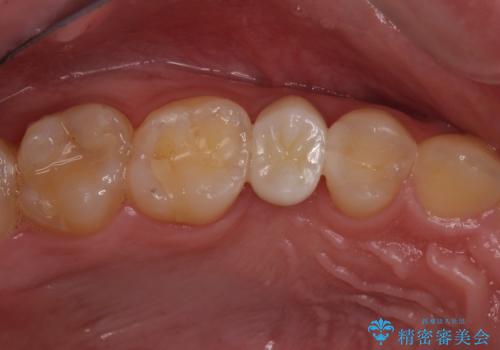

右上もう1本と左上は虫歯治療(セラミックインレー、セラミッククラウン)を行いました。

痛いところがなくなり、患者様には大変満足して頂きました。